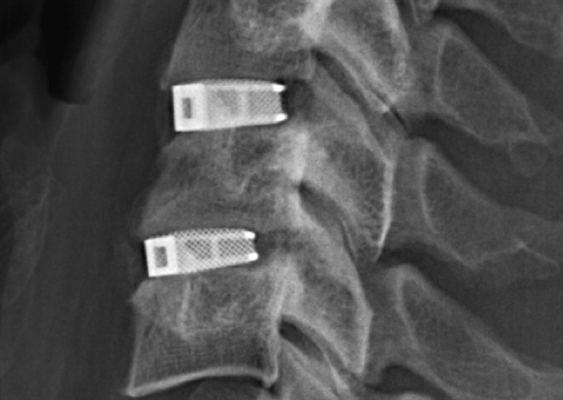

Кейджы межпозвоночных дисков поясничного отдела.

В преобладающем количестве подобные операции заключаются в достижении полного обездвиживания патологических уровней за счет прочного скрепления двух или более позвонков ригидными конструкциями. Это позволяет позвонкам с течением некоторого времени (от 3 до 6 месяцев) срастись между собой и образовать единый неподвижный костный блок. То есть, на прооперированном поле подвижность между позвонками будет заблокирована, а человек сможет нормально двигаться и ходить, не испытывая при этом боли и прочих неврологических расстройств.

Метод PLIF подразумевает удаление отростков с двух сторон от позвонка. После этого осуществляется радикальная дискэктомия. По обеим сторонам позвонка устанавливаются кейджи.

Иногда их заменяют расширяющимися имплантатами. Поскольку они обладают меньшими размерами, нейрохирургу достаточно провести медиальную двустороннюю фасетэктомию (удаление фасеточных суставов) и удалить только студенистое ядро диска. Такие имплантаты оснащены винтами. Их раскручивают специальным ключом, благодаря чему кейджи прочно фиксируются в заданном положении.